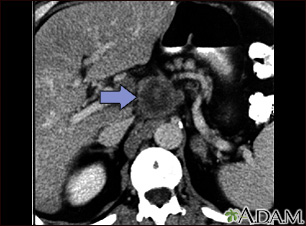

Pancreatic cancer, CT scan

Pancreatic cancer, CT scan

A CT scan of the upper abdomen showing a tumor (pancreas carcinoma) in the head of the pancreas, seen here in the middle of the picture.